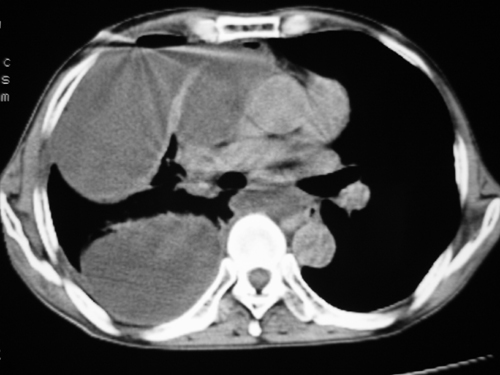

以下是引用yangyudong333在2008-4-29 5:46:00的发言:[br]1左上叶结节呈分叶状,边缘毛刺,考虑肺癌并纵隔淋巴结转移可能性大,结核待排,[br] [br]2右侧多发包裹性胸腔积液

以下是引用zsl6918在2008-4-29 9:15:00的发言:[br]右侧包裹性积液穿刺术后改变,肺内多发结节不除外转移可能。建议查胸水,问病史。